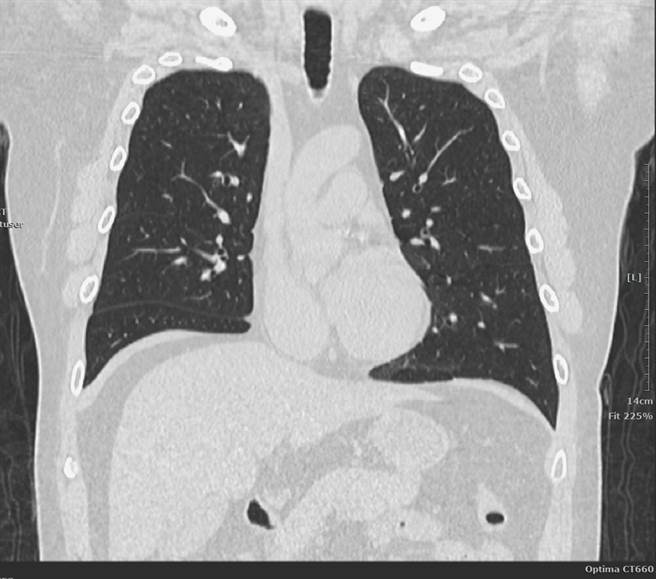

中荣埔里分院表示,近年愈来愈多没有吸菸的民眾罹患肺癌,推测可能和空污、油烟等因素有关,民眾若透过肺部低剂量电脑断层扫描(LDCT),检查过程仅需10分钟,且检查前不用禁食和禁水,辐射量仅是传统电脑断层的1/5, 还能比胸部X光检查提早5年至10年发现肺癌。

根据国健署统计,民眾不舒服就医被诊断出肺癌,通常都太晚了,大约有6成已转移,甚至无法手术治癒,抽菸、吸二手菸、易吸入厨房油烟、废气等高度空污环境,或有其他癌症病史、近亲罹患肺癌等都是高危险群,为了提高癌症早期发现率,卫福部7月1日开办「肺癌早期侦测计画」。

中荣埔里分院指出,LDCT自费要价5千到8千元不等,政府针对「肺癌家族史」及「重度吸菸史」,提供2年1次的免费LDCT筛。具「肺癌家族史」的50岁以上男性或45岁以上女性,「重度吸菸史」即50岁以上每年抽30包以上香菸民眾,有意愿戒菸或戒菸15年内之重度吸菸者;建议检查结果异常的民眾配合医师建议定期追踪。